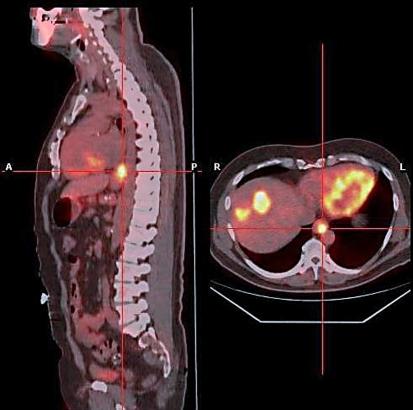

Metastasis to the oesophagus is most frequently described in association with lung or breast cancer. Diagnosis is frequently complicated as often only normal tissue is present in endoscopic biopsy specimens. Although oesophagectomy for metastasis has been described, few patients are suitable for curative resection. We report the case of a 62-year-old man who developed an oesophageal metastasis from colorectal cancer and review the available literature.

食管癌转移最常被描述为与肺癌或乳腺癌相关。诊断常常很复杂,因为在内镜活检标本中通常仅存在正常组织。尽管已经报道了针对转移灶的食管切除术,但很少有患者适合进行根治性切除。我们报告了一例62岁男性发生结直肠癌食管转移的病例,并对现有文献进行了综述。